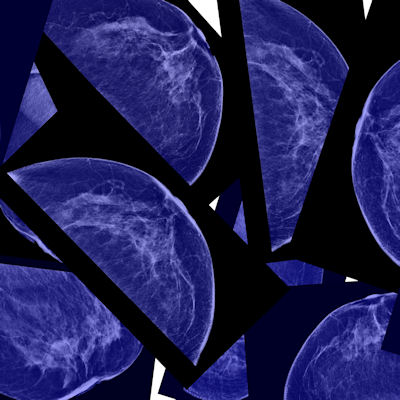

Almost 60% of women over the age of 40 skip annual mammograms, and almost a quarter (23%) say they've never had one, according to a survey conducted by MedStar Health in Maryland, MD.

The survey results come at time when breast cancer diagnoses continue to increase, according to the American Cancer Society. And in May, the U.S. Preventive Services Task Force (USPSTF) lowered the recommended age for biennial screening from 50 to 40.